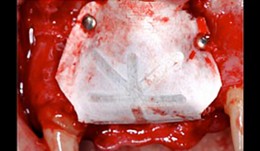

Bone Transfer

Streckbein, RolandContent: Description of system and instruments. The patient had a considerable bone deficit at tooth 21. Augmentation was therefore required and was carried out using calibrated instruments. The augmentation site was prepared using instruments that matched the tools used to harvest the cylindrical bone graft at the donor site. This perfect match between the augmentation region and the bone transplant accelerated osseointegration, there by shortening the required waiting time for implant placement. -